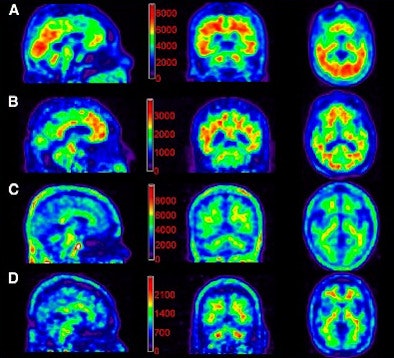

| Florbetapir images for 111-MBq and 370-MBq dose groups acquired in a 10-minute PET scan 50 minutes after injection. Counts per pixel are shown on color scale for purposes of this figure, but were not available to readers. Image A is a 370-MBq dose in an Alzheimer's subject. The average image quality rating was 4. Image B shows a 111-MBq dose in an Alzheimer's subject, with an average image quality rating of 2. Image C shows a 370-MBq dose in a control subject. The average image quality rating was 4. Image D is a 111-MBq dose in a control subject, with an average image quality rating of 2. Images courtesy of the Journal of Nuclear Medicine. |

The authors did note a difference in visual quality between the 370-MBq dose and 111-MBq dose, with the latter showing slightly lower image quality. However, "no statistical significance was achieved in this relatively small sample of subjects," they wrote.

Readers interpreting the PET florbetapir scans were able to identify all Alzheimer's subjects as beta-amyloid positive and all control subjects as beta-amyloid negative.